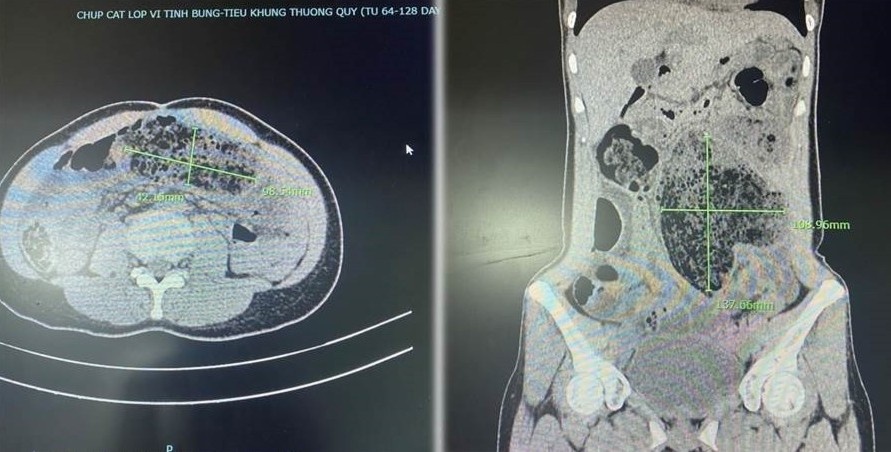

Các bác sĩ chỉ định chụp CT ổ bụng, xác định chị bị tắc ruột do bã thức ăn, nghĩ đến vì ăn mít. Ảnh: Bích Huệ.

Rạng sáng 25/6, bệnh nhân nhập viện. Các bác sĩ chỉ định chụp CT ổ bụng, xác định chị bị tắc ruột do bã thức ăn, nghĩ đến vì ăn mít.

Kết quả chụp hình ảnh Cắt lớp vi tính (CT-Scan) phát hiện đoạn ruột phình to với kích thước 4,2 cm x 9,8 cm; 13,8 cm x 10,9 cm chứa nhiều bã thức ăn. Ảnh: BVCC.